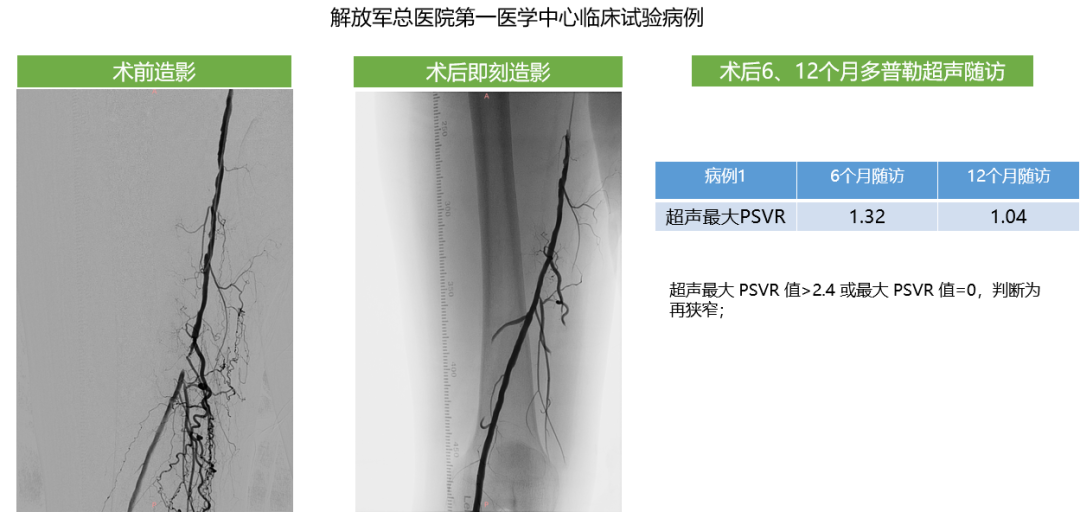

约束型药球病例1

血运重建发生在靶病变且合并介入治疗处理,即为临床驱动的靶病变血运重建。 超声最大 PSVR 值>2.4 或最大 PSVR 值=0,判断为再狭窄;若最大 PSVR 值缺失,且该受试者大截肢,判断为再狭窄。